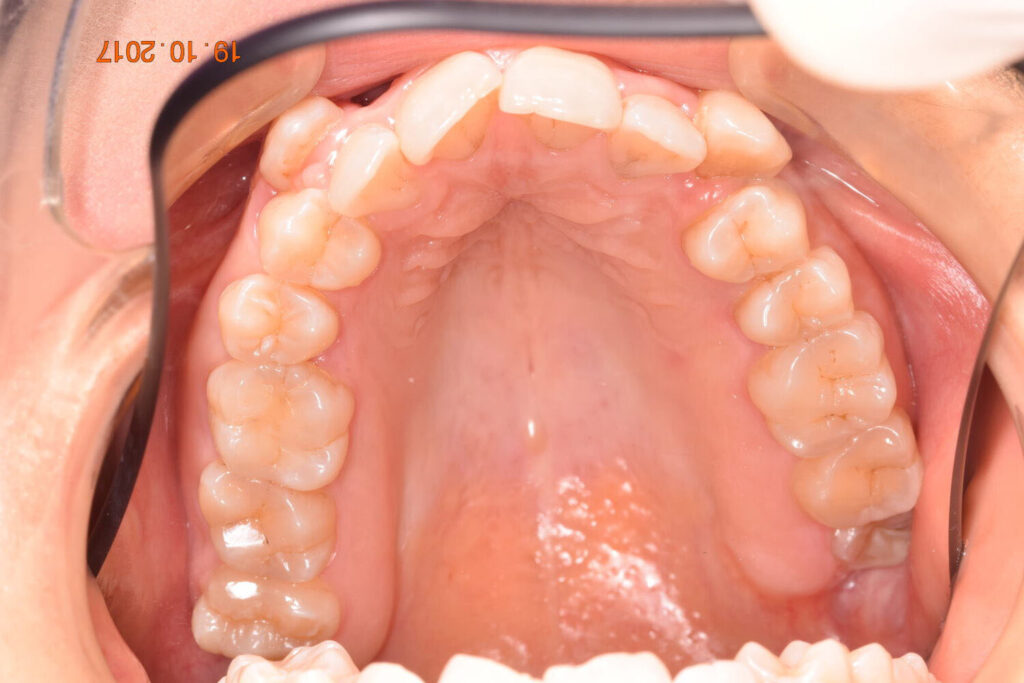

A 27-year-old female patient presented with class III malocclusion, 15 mm crowding in the upper arch, an anterior open bite, a lateral crossbite, and a total ABO score of 29. Her facial profile was straight with a retrusive maxilla, and the upper and lower incisors were retroclined. An extreme lack of midface support was also noted, and the constricted dental arches resulted in a poor smile width and dark buccal corridors. No myofunctional investigations were performed at the time, as they were initially considered unnecessary.

Dr. Coca’s treatment plan followed the Biology First Orthodontics approach, which aims to minimize biological interventions. The treatment plan avoided extractions, stripping, TADs, corticotomy, and RPE. Given the facial requirements, a non-extraction treatment option was chosen.

The treatment began in 2017. Given the patient’s preference for less visible brackets, Damon Clear brackets were selected. High torque upper cuspids and low torque upper incisors were chosen to offer the best torque control for upper arch development. For the lower arch, there were no alternative bracket configurations available. Bite turbos were applied to the upper second molars.